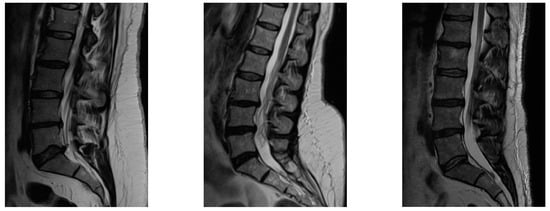

2.3. Intervention and Follow-Up